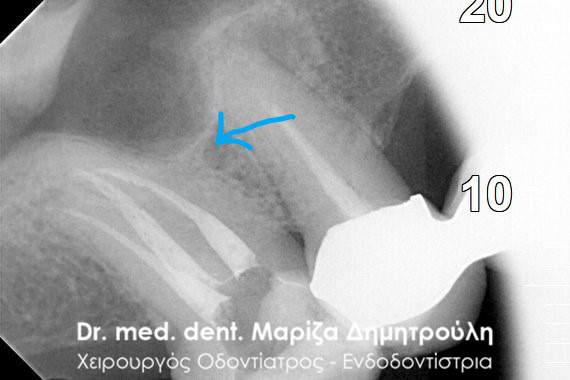

BEFORE

BEFORE